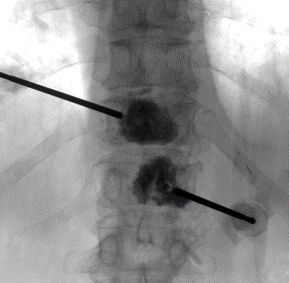

Vertebral body tumor access

AveCure® microwave ablation system is successfully used to treat and relieve pain from metastatic vertebral-body tumors and bone cement is used to fill the remaining cavity to restore the mechanical structure. The procedure is minimally invasive. A bone cannula is inserted through a skin incision to access the tumor and the patient is left with a small hole in the skin, which quickly heals with almost no scar after the procedure. The AveCure® ​system utilizes a smart antenna in either probe or catheter format and a microwave energy controller to select the correct size, temperature and timer settings appropriate for safe, effective and predictable treatment.